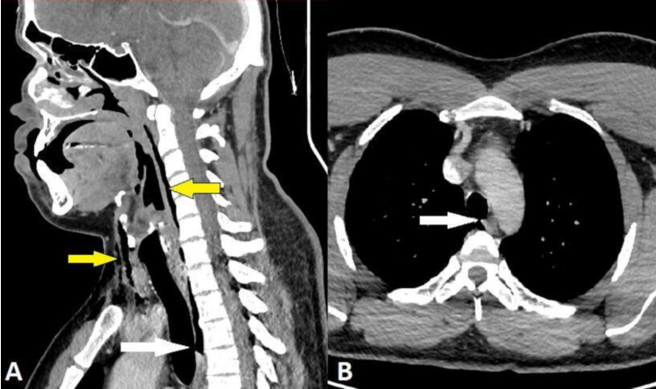

醫院檢查顯示男子的氣管出現一道撕裂傷。(圖/翻攝自BMJ官網)

這名30多歲男子被送到急診室時極度疼痛,頸部兩側腫脹且活動困難,醫師檢查時還可聽見微弱的劈啪聲,不過不影響呼吸、吞嚥與說話。頸部X光檢查顯示男子出現皮下氣腫,代表有空氣堵在皮膚最深層組織下方;電腦斷層掃描結果則顯示,穿孔部位在他第三和第四節頸椎之間,還有空氣堵塞在兩顆肺之間的胸腔裡。